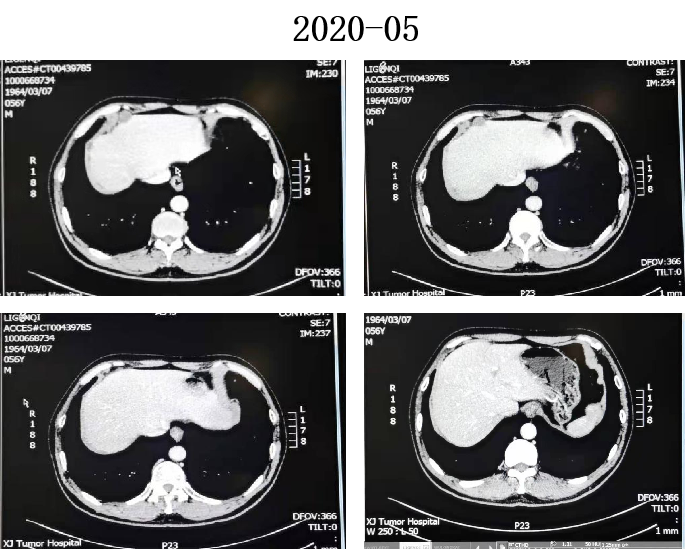

2022-05 复查CT

乙状结肠癌术后改变,同前相仿;左侧盆腔腰大肌旁混杂密度结节,多系术后改变,同前相仿。

肝尾状叶边缘、胰腺上方钙化结节,同前相仿;腹盆腔少量积液,腹膜转移,盆腔积液减少,余较前略较前变化不大。

2022-06 腹部平片

右中上腹肠管扩张并少许气液平面,考虑肠梗阻。